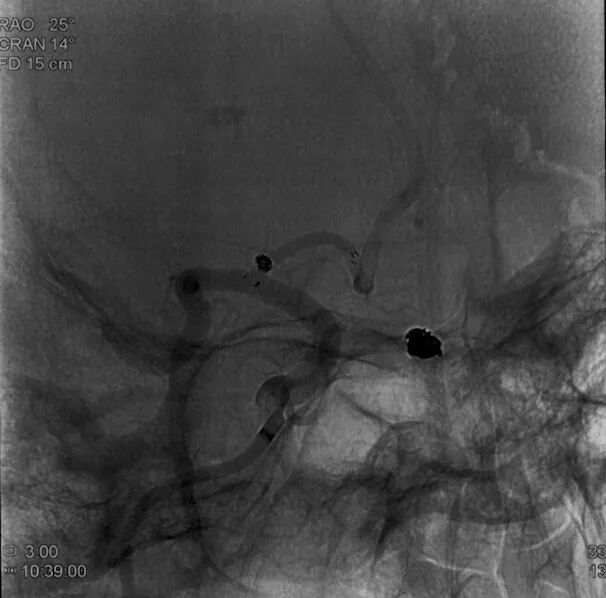

术前外院 DSA 2025-02

箭头所指右侧A1微小动脉瘤

术后正侧位造影:Raymond Ⅲ级

术后支架重建:支架打开良好,近端Marker位于颈内动脉分叉处

术后Vaso CT未见出血,患者神清语利,神经系统查体阴性。